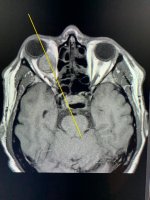

Była to niezwykle skomplikowaną operacja usunięcia olbrzymiego guza przyśrodkowej części oczodołu.

- Podczas tej operacji zastosowaliśmy dwie techniki operacyjne: „atakowaliśmy” endoskopowo guz od strony nosa, a pod powiększeniem ezgzoskopowym, z dojścia od przodu przez spojówkę oka, odpreparowaliśmy go od niezwykle delikatnych nerwów i naczyń oczodołu - tłumaczy dr hab. Tomasz Łysoń, z Kliniki Neurochirurgii. - Z całą pewnością jest to pierwsza tego typu operacja w Polsce, a zapewne również i na świecie. Operując oczodół pod mikroskopem, nie moglibyśmy wprowadzić do nosa endoskopu, gdyż te dwa urządzeni po prostu by się w tym małym polu operacyjnym nie zmieściły.